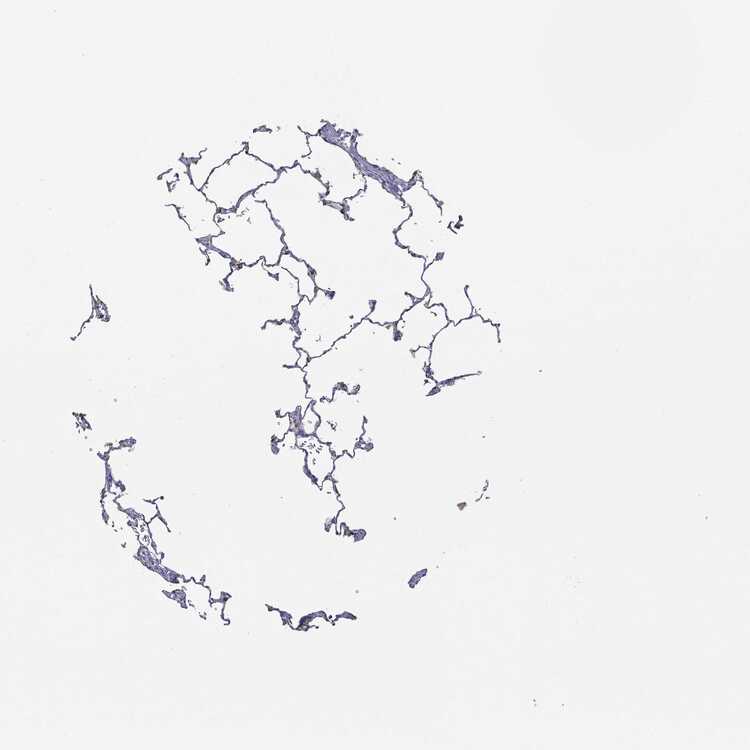

LUNG - Antibody stainingi

Antibody staining in the annotated cell types in the current human tissue is reported as not detected, low, medium, or high, based on conventional immunohistochemistry profiling in selected tissues. This score is based on the combination of the staining intensity and fraction of stained cells.

Each image is clickable and will lead to virtual microscopy that enables deeper exploration of all samples and also displays staining intensity scores, fraction scores and subcellular localization as well as patient and tissue information for each sample.

Antibody HPA004179Antibody HPA007235Antibody HPA008855Antibody CAB000036Antibody CAB001986Antibody CAB080102Antibody CAB080103

Alveolar cells HighNot detectedMedium-MediumNot detectedMedium

Alveolar cells type I ---High---

Alveolar cells type II ---High---

Endothelial cells ---Not detected---

Macrophages Not detectedNot detectedLowLowLowNot detectedHigh